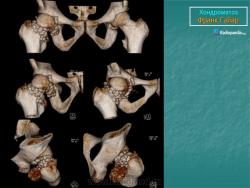

Хондроматоз внутрисуставной (синовиальный)

Хондроматоз